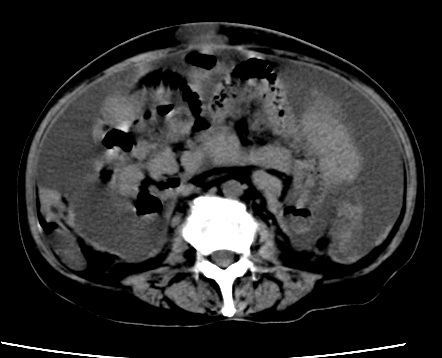

标题: CT23975:女61岁,腹部不适,明显消瘦 [打印本页]

标题: CT23975:女61岁,腹部不适,明显消瘦

既往5年前卵巢癌行子宫及附件切除,右乳癌术后一年,考虑腹膜转移?

大量腹水,考虑腹膜转移。肝脏低密度灶。1囊肿,2转移。

1)结合病史,考虑腹膜及网膜转移瘤。2)肝脏多发性低密度灶,不排除转移瘤。3)大量腹水。

考虑卵巢癌行子宫术后复发,并肝、腹腔 、大网膜转移可能性大。

大量腹水。